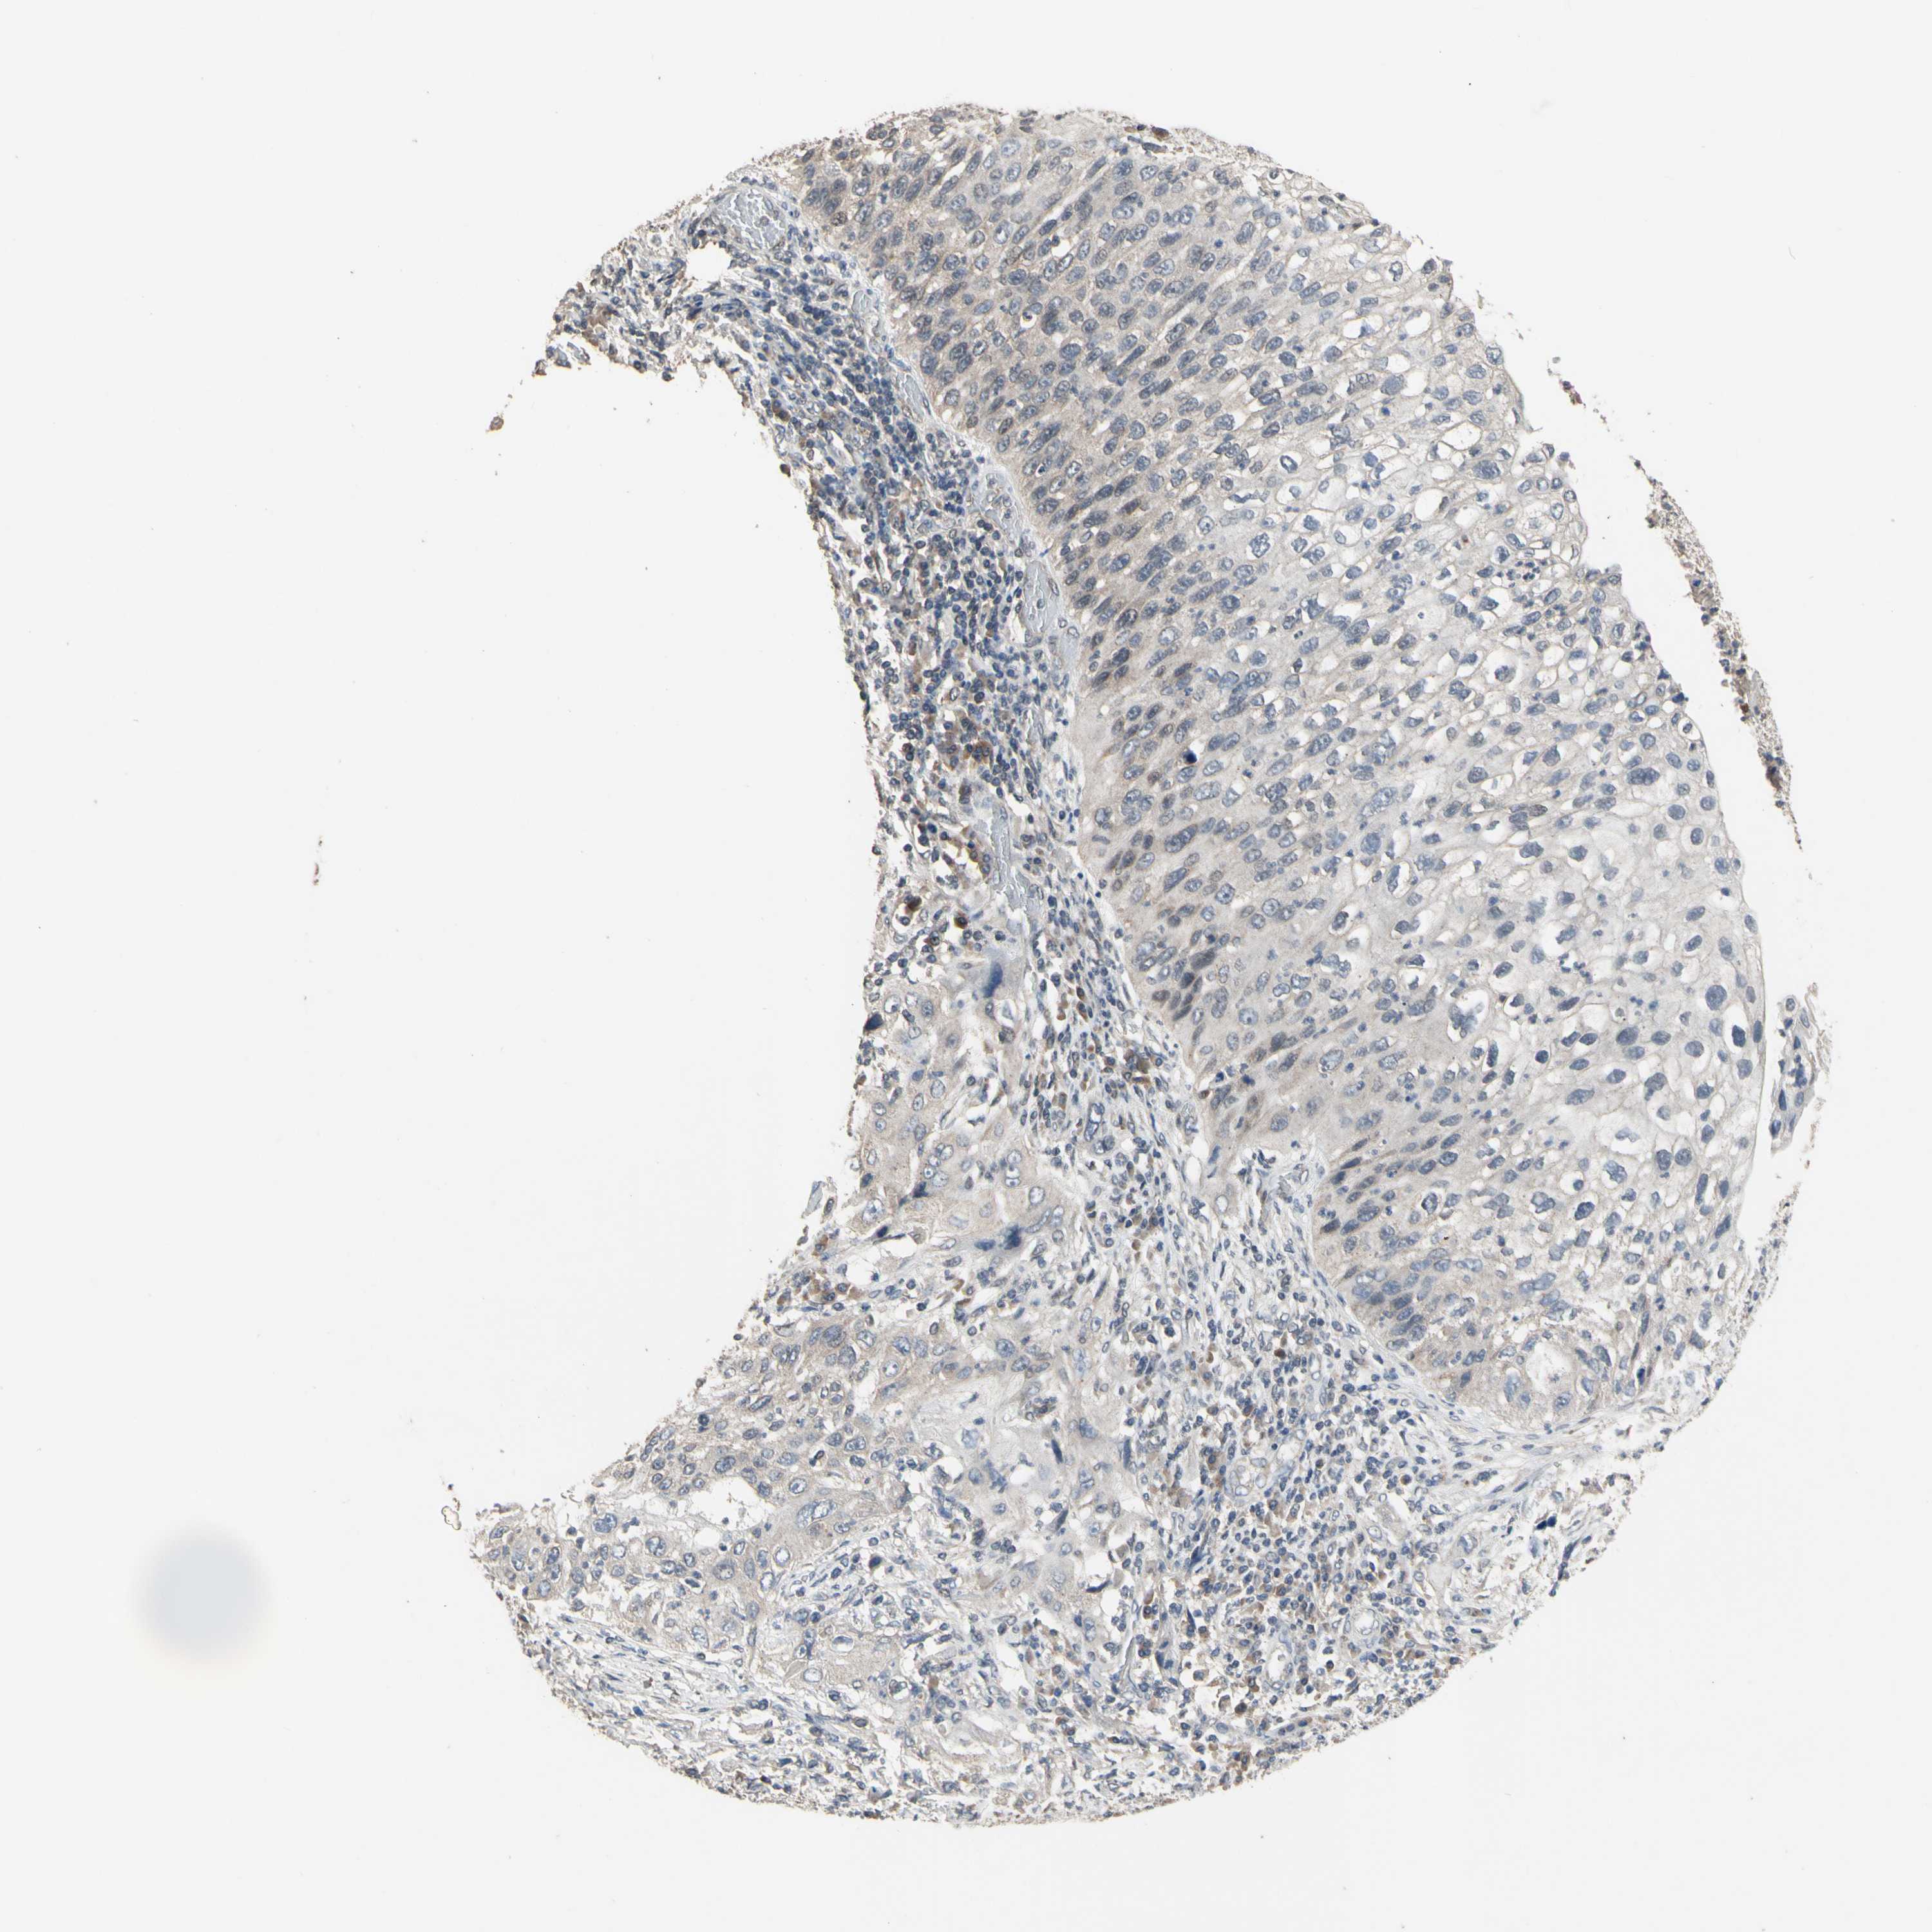

LUNG ADENOCARCINOMA (VALIDATION) - Interactive survival scatter ploti

The Survival Scatter plot shows the clinical status (i.e. dead or alive) for all individuals in the patient cohort, based on the same data that underlies the corresponding Kaplan-Meier plots. Patients that are alive at last time for follow-up are shown in blue and patients who have died during the study are shown in red.

The x-axis shows the expression levels (FPKM) of the investigated gene in the tumor tissue at the time of diagnosis. The y-axis shows the follow-up time after diagnosis (years). Both axes are complimented with kernel density curves demonstrating the data density over the axes. The top density plot shows the expression levels (FPKM) distribution among dead (red) and alive patients (blue). The right density plot shows the data density of the survived years of dead patients with high and low expression levels respectively, stratified using the cutoff indicated by the vertical dashed line through the Survival Scatter plot. This cutoff is automatically defined based on the FPKM cutoff that minimizes the p-score. The cutoff can be changed by dragging the vertical line or by entering a cutoff value in the square labeled "Current cut-off".

Under the Survival Scatter plot the p-score landscape (black curve; left axis) is shown together with dead median separation (red curve; right axis). Dead median separation is the difference in median mRNA expression between patients who have died with high and low expression, respectively. It is calculated as follows: median FPKM expression of dead patients with high expression - median FPKM expression of dead patients with low expression. This is intended to aid the user in visually exploring custom cutoffs and the associated p-scores and dead median separation.

Individual patient data is displayed and can be filtered by clicking on one or more of the category buttons on the top of the page. Categories describing expression level and patient information include: high, low, alive, dead, female, male and tumor stages. The scale of the x-axis can be toggled between linear and log-scale by clicking on the "x log" button. Mouse-over function shows TCGA ID, patient information and mRNA expression (FPKM) for each patient.

& Survival analysisi

Kaplan-Meier plots summarize results from analysis of correlation between mRNA expression level and patient survival. Patients were divided based on level of expression into one of the two groups "low" (under cut off) or "high" (over cut off). X-axis shows time for survival (years) and y-axis shows the probability of survival, where 1.0 corresponds to 100 percent.

ZNF174 is not prognostic in Lung Adenocarcinoma (validation)

Best expression cut offi

Based on the FPKM value of each gene, patients were classified into two groups and association between prognosis (survival) and gene expression (FPKM) was examined. The best expression cut-off refers the FPKM value that yields maximal difference with regard to survival between the two groups at the lowest log-rank P-value. Best expression cut-off was selected based on survival analysis .

When clicking on this number, the vertical dashed line indicating cut-off, the interactive survival plot, and the Kaplan-Meier curve will be adjusted to show results based on the best expression cut-off.

: 14.61

P scorei

Log-rank P value for Kaplan-Meier plot showing results from analysis of correlation between mRNA expression level and patient survival.

N/A

TCGA RNA samplesi

RNA-seq data is reported as average FPKM (number Fragments Per Kilobase of exon per Million reads), generated by the The Cancer Genome Atlas (TCGA) .

Normal distribution across the dataset is visualized with box plots, shown as median and 25th and 75th percentiles. Points are displayed as outliers if they are above or below 1.5 times the interquartile range. FPKM values of the individual samples are presented next to the box plot.

Average pTPM 11.7

Number of samples 105